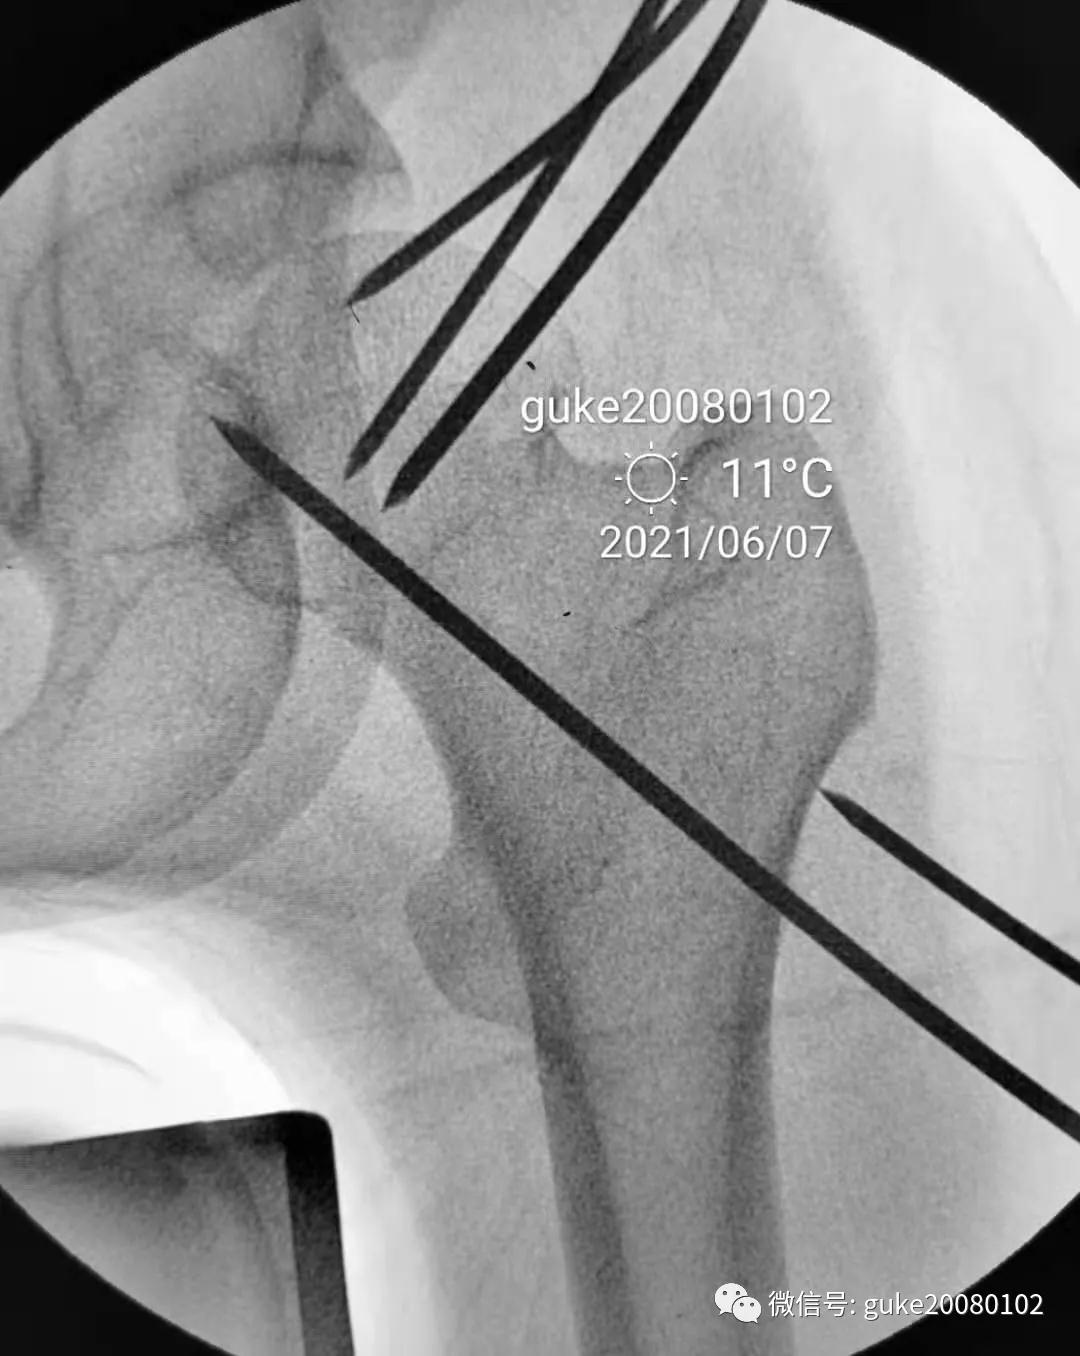

1.顺导针切开皮肤后,空心钻大转子外侧壁开口。

2.拧入三枚直径7.3mm空心钉,并逐步加压,稳定骨折断端。

最后透视: